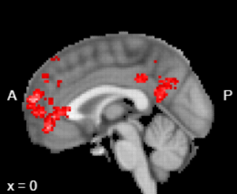

첫 번째로 연구자들은 '자기'와 관련된 특징을 판단하도록 했을 때, 내측 전전두피질이라는 구조물에서 차지하고 있는 작은 뇌 영역이 활성화되는 것을 확인했습니다. 이 부위의 일부는 '자기'와 관련된 정보를 처리할 때 특별히 중요한 역할을 담당합니다.

'자기'에 대한 정보를 주요하게 처리하는 뇌 부위. 뇌를 반으로 쪼갰을 때, 앞쪽 가운데에 작은 부위를 차지합니다